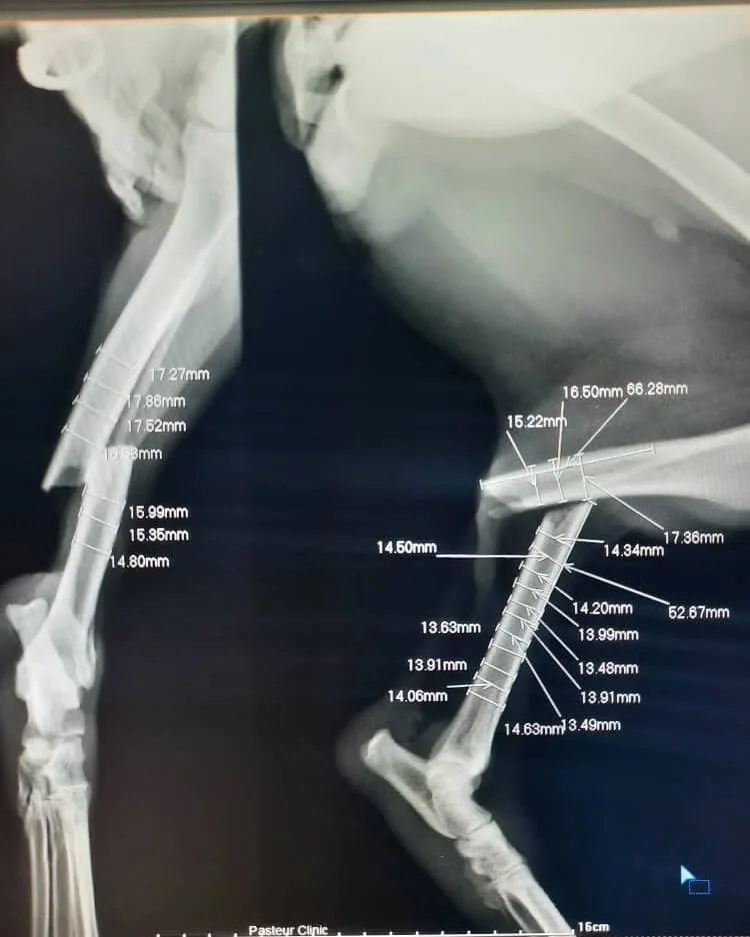

She was struck by a car and left gravely injured on the roadside. Both her front and back legs were snapped completely, the broken bones pushed out of alignment and stabbing into muscle, just as the x-ray later revealed. The pain was unimaginable.

When the shelter team reached her, they rushed her to surgery. A miracle-worker of a veterinarian carefully aligned the shattered bones and pieced them back together with plates and screws. It was a long, delicate operation, but it gave her the chance not just to live — but to walk again.